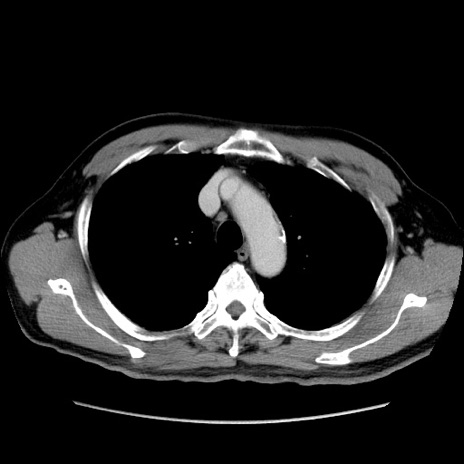

症例34(横断像)

【症例】60歳代 男性

【主訴】右鼠径部膨隆

【現病歴】1年程前より右鼠径部膨隆あり。自己にて還納可能だったため放置していた。3時間前より右鼠径部の脱出を認め、還納困難となり受診。

【身体所見】右鼠径部に小児頭大の膨隆あり。弾性硬であり、用手還納は困難。左鼠径部にも膨隆を認める。脱出はなし。